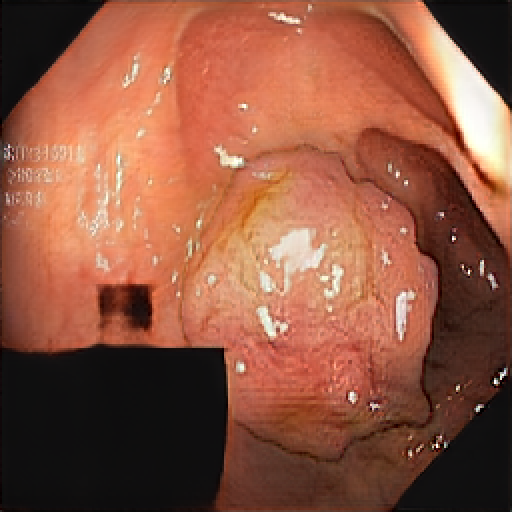

We have used a polyp dataset published with HyperKvasir dataset [51], which consists of polyp findings extracted from endoscopy examinations. HyperKvasir contains polyp images with corresponding segmentation masks annotated by medical experts. We use only this polyp dataset as a case study because of the time and resource-consuming training process of the SinGAN-Seg pipeline. However, the SinGAN-Seg model and pipeline can be used for any segmentation dataset.

A few sample images and the corresponding masks of the polyp dataset in HyperKvasir are shown in Fig 2. The polyp images are RGB images. The masks of the polyp images are single-channel images with white () for true pixels, which represent polyp regions, and black () for false pixels, which represent clean colon or background regions. In this dataset, there are different sizes of polyps. The distribution of polyp sizes as a percentage of the full image size is presented in the histogram plot in Fig 3, and we can observe that there are more relatively small polyps compared to larger polyps. Additionally, a subset of this dataset was used to prove that the performance of segmentation models trained with small datasets can be improved using our SinGAN-Seg pipeline, and the whole dataset was used to show the effect of using SinGAN-Seg generated synthetic images instead of a large dataset which has enough data to train segmentation models. In this regard, this dataset was used for two purposes: